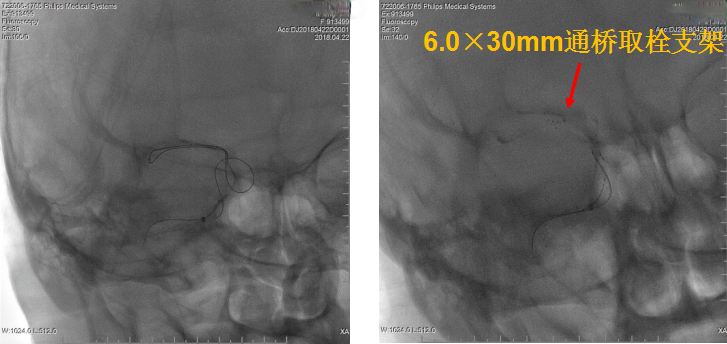

考虑血栓负荷量大,遂采用双支架取栓技术。

该病例为颈内动脉C1段远端闭塞,血栓负荷率大,我们采用常规的SWIM技术(支架取栓+抽栓),但是效果不佳,于是改为双支架串联技术取栓,达到mTICI 2b级血管再通效果。

该病例提示通桥取栓支架不仅可以应用于常规支架取栓,在双支架取栓应用中,也能取得较好效果。

针对本例患者,选择了单纯使用导引导管的双支架串联式释放同时局部并联释放技术,双重支架叠加可以增加支架释放的径向支撑力,同时也增加了支架网丝对血栓的嵌入效应、接触面积和血栓的缠绕能力,快速将血栓拉出体外,提高了开通效率,并最终获得良好开通效果和3个月良好预后。